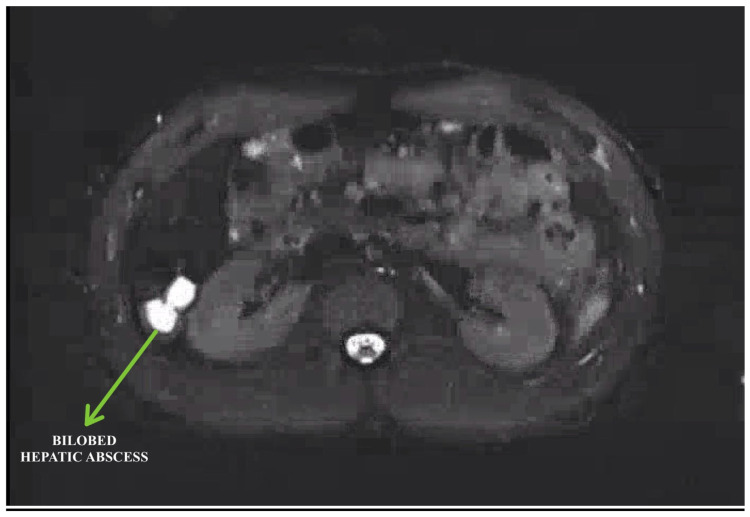

A 'Fluke' Diagnosis: Suspecting Fascioliasis as a Rare Cause of Hepatic Abscess.

Hepatic abscess is a rare complication of fascioliasis, with fewer than 50 reported cases worldwide. The diagnosis requires a high degree of suspicion and is often identified after extensive investigation leading to delays in treatment. With this case report, we aim to highlight the need for a higher index of suspicion in non endemic regions like the USA, especially in cities with large immigrant populations. Given the ease and success rates of treatment with oral triclabendazole, the morbidity from unnecessary invasive testing and disease burden is preventable with a thorough evaluation and targeted clinical assessment.